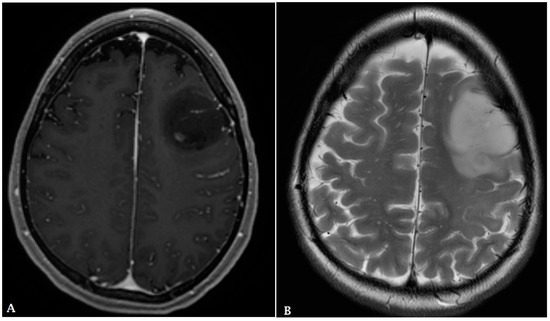

- Haldorsen, I.; Espeland, A.; Larsson, E.-M. Central Nervous System Lymphoma: Characteristic Findings on Traditional and Advanced Imaging. Am. J. Neuroradiol. 2011, 32, 984–992. [Google Scholar] [CrossRef]

- Kickingereder, P.; Wiestler, B.; Sahm, F.; Heiland, S.; Roethke, M.; Schlemmer, H.-P.; Wick, W.; Bendszus, M.; Radbruch, A.; Jalaguier-Coudray, A.; et al. Primary Central Nervous System Lymphoma and Atypical Glioblastoma: Multiparametric Differentiation by Using Diffusion-, Perfusion-, and Susceptibility-weighted MR Imaging. Radiology 2014, 272, 843–850. [Google Scholar] [CrossRef]